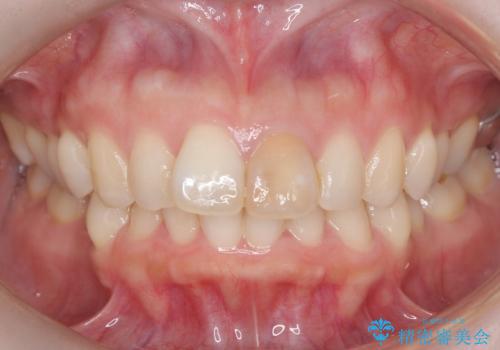

前歯の変色を改善し、本来の自然な美しさへ

- 以前の根管治療後に生じた左上1番の前歯の変色を気にされて来院されました。患者様のご希望を伺い、オールセラミッククラウンによる審美修復を提案。既根管治療歯であるため、土台の状態や周囲の歯の色調を詳細に分析し、患者様の顔貌に調和した自然で美しい口元を実現するための治療計画を立てました。